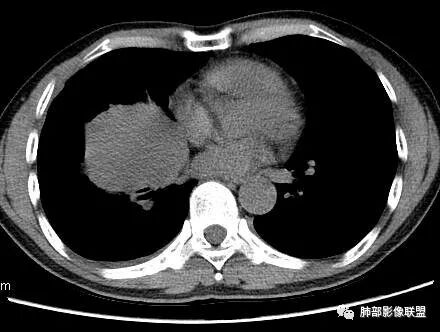

3.肿块常常较大,甚至巨大,病灶边界一般清楚,影像上常有假包膜样结构、有膨胀性生长的特点,影像科医师有时甚至会纠结其来源于肺部或是胸壁纵隔。常见的肺癌肿块,很少有机会能长成这样的规模。

4.边缘可以有浅切迹,部分病灶会有铸型样外观,但大体十分圆钝,不会出现典型的分叶和毛刺,也很少会出现胸膜牵拉。支气管常推移,有明显的支气管阻塞时也较少观察到相关的阻塞性炎症。

5.病灶密度大多不均,不规则坏死液化,少数病例出现钙化。增强扫描常观察到由外而内的厚壁不均匀强化,中央半岛样强化等等,厚壁中或实性区常能显示血管影。一些病灶中央呈现边界清楚囊样变。

6.病灶侵犯胸膜时可以出现胸水,病灶可以侵犯胸壁并引起相应临床症状。